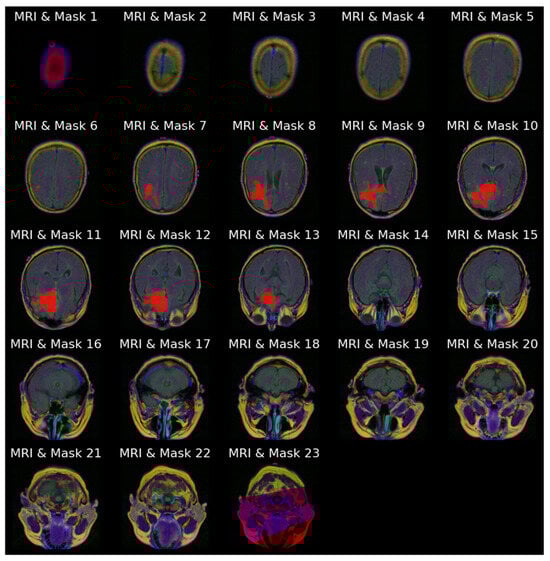

Figure 4a stacks all 23 slices available for the same patient in cranio-caudal order. The sequence reveals how the cranial vault initially appears tumor-free and gradually opens to reveal the lesion, which then enlarges before disappearing again. Figure 4b presents the ground truth masks for those 23 slices without the underlying MRI signal, emphasizing the sparsity of positive pixels in many frames.

Figure 4.

Anatomical order visualization for patient with ID “TCGA_CS_4941_19960909”: (a) Complete set of 23 axial FLAIR slices; (b) ground truth tumor masks.

Figure 5 combines the two views of Figure 4, overlaying every mask on its corresponding MRI slice-image, reinforcing the spatial coherence of the annotations that will later be used as a qualitative benchmark for model outputs.

Figure 5.

Image–mask (red) overlays for all 23 slices for patient with ID “TCGA_CS_4941_19960909”.